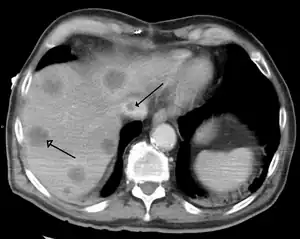

| Budd–Chiari syndrome secondary to cancer, note clot in the inferior vena cava and the metastasis in the liver | |